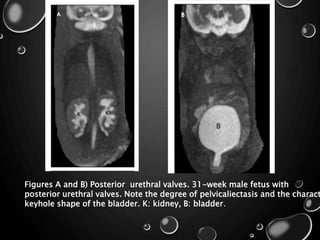

• THE COMMON GU INDICATORS FOR FETAL MR INCLUDE

• POLYCYSTIC KIDNEY DISEASE ,

• MULTICYSTIC DYSPLASTIC KIDNEY ,

• URETEROPELVIC JUNCTION (UPJ) OBSTRUCTION , AND

• POSTERIOR URETHRAL VALVES IN THE MALE FETUS

Figures A and B) Posterior urethral valves. 31-week male fetus with

posterior urethral valves. Note the degree of pelvicaliectasis and the charact

keyhole shape of the bladder. K: kidney, B: bladder.